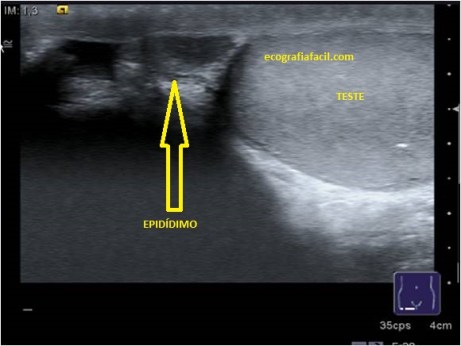

Una vez que el paciente esté preparado sonda en mano y gel abundante sobre todo si el paciente tiene mucho bello púbico, buscaremos en longitudinal el teste derecho hasta que veamos que está en un corte central, entonces subiremos en ese eje largo del teste hasta llegar al epidídimo, realizaremos foto del teste y el epidídimo en longitudinal y la medición en este plano. Puede hacerse en dos fotos distintas, por un lado el epidídimo y por otro el Teste.

Localización de epidídimo.

Valoraremos igualmente todo el recorrido del Epidídimo que será lateral al teste, pero pegado a él y discurre desde el polo superior al inferior del teste.

El epidídimo es isoecogénico con el teste y es pseudotriangular y sito en el polo superior del testículo.